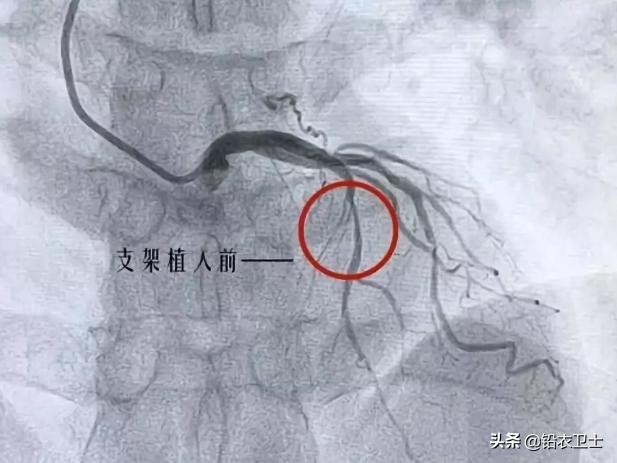

5.经皮冠状动脉腔内成形术(PTCA)+支架术对于挽救急性心肌梗塞病人的生命、提高救治成功率、改善心肌梗塞病人的预后及提高生活质量是成 效显著,对于改善较为稳定的冠心病患者的预后、生活质量及提高患者耐受各种事件打击的能力是十分有效的。